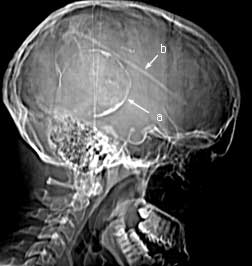

CT scout

Findings:

Round, peripherally calcified lesion (a) at the posterior aspect of the skull. Shunt tube in place (b).